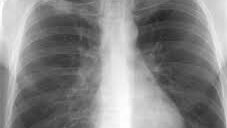

Видно ли на флюорографии рак, туберкулез и последствия курения

Видно ли на флюорографии, что человек курит – совсем не тот вопрос, который должен интересовать обследуемого человека. Но заядлым курильщикам хотелось бы точно знать, как проявятся последствия курения и не спутает ли их врач с симптомами туберкулезных поражений. Флюорография – это современное диагностическое исследование, основанное на просвечивании грудной клетки рентгеновскими лучами. Изображение теней в уменьшенном виде переносится на пленку. Результаты оценивает врач-фтизиатр и в первую очередь определяет наличие или отсутствие туберкулеза...